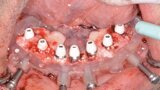

Fig. 16: Mandibular bone levelling guide.

Fig. 17: Mandibular implant surgical

guide.